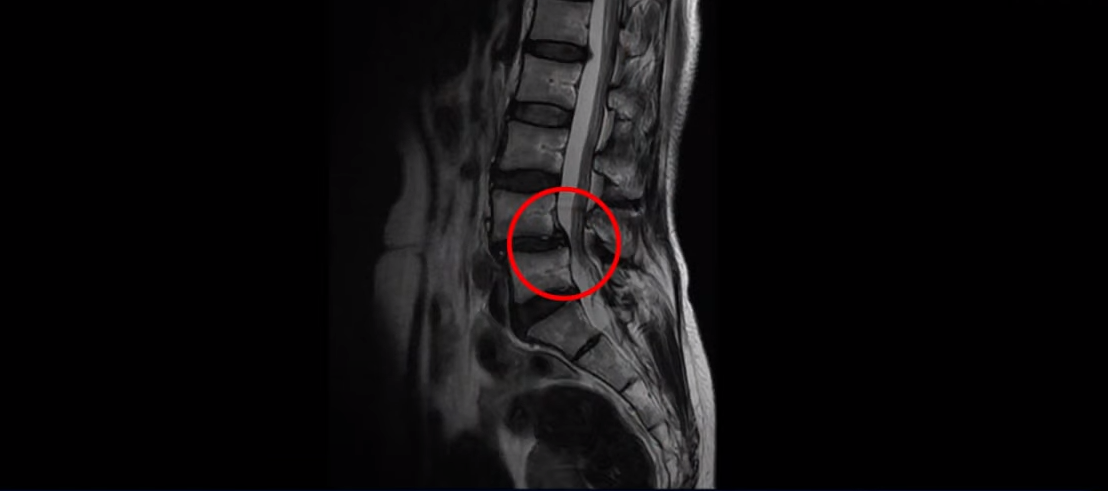

또 한 가지 추가로 말씀드릴 건 이 환자분은 전방전위증으로 인한 만성적인 허리통증을 수년간 겪고 계신 분이었습니다.

이번에 엉덩이 근육 파열로 인한 재활치료를 받으면서 동시에 전방전위증을 동반한 만성 허리통증 치료도 함께 받으셨습니다. 우선 이 환자분의 얘기를 직접 들어보시겠습니다.